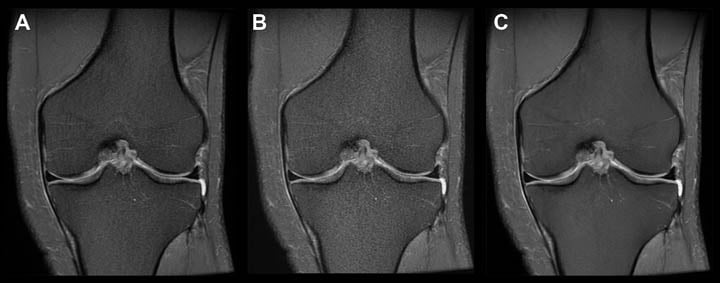

UMass is piloting several FDA approved AI algorithms developed by aidoc, a vendor specializing in diagnostic algorithms that highlight acute abnormalities on CT. This AI based software runs in the background as the radiologist works, flags a case in the reading queue as high priority if an abnormality is detected and produces a color coded overlay to indicate the abnormality.

- CT angiogram of the chest with bilateral pulmonary emboli.

- AI based software highlights the emboli, color coded in red.

Data collected at UMass Memorial Healthcare in collaboration with aidoc.